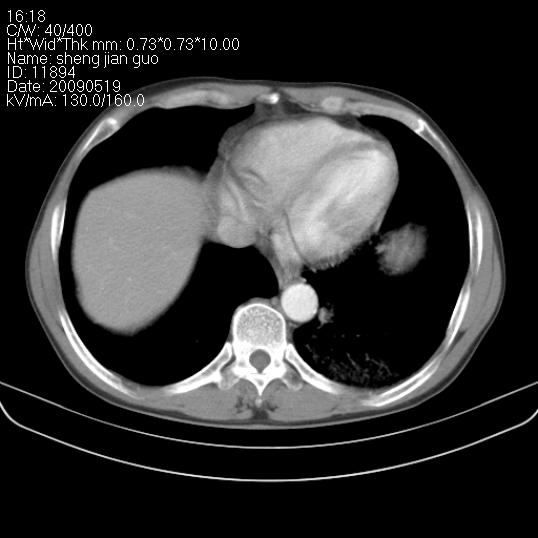

以下是引用zjzjr在2009-5-19 17:25:00的发言:[br]支持楼主考虑,另左肺下叶阻塞性炎症。

以下是引用zhao_bin2008在2009-5-19 17:48:00的发言:[br]支持左肺下叶周围型肺癌并阻塞性肺炎。

以下是引用杀毒软件在2009-5-19 17:36:00的发言:[br]支持楼主

以下是引用zsl6918在2009-5-20 7:10:00的发言:[br]左侧中心型肺癌!